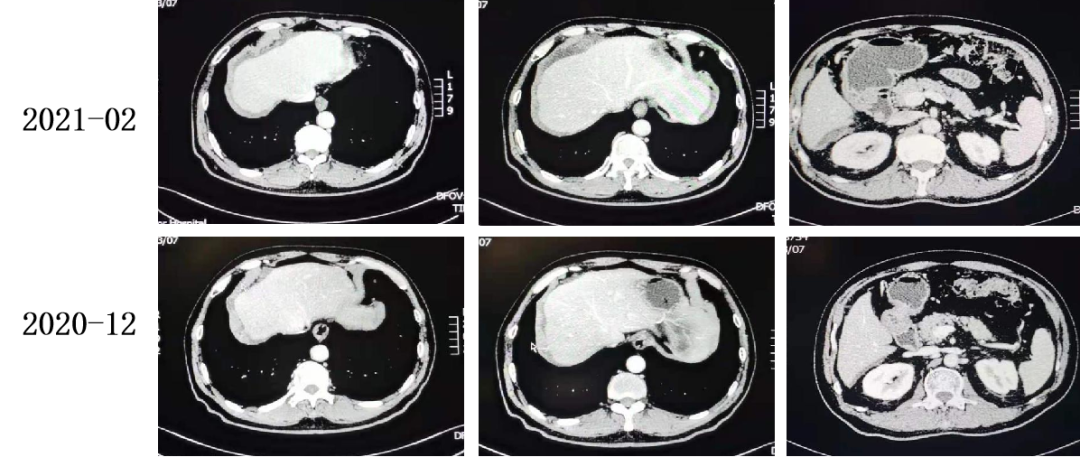

2021-02 复查CT:腹盆腔少量积液,腹膜增厚,较前进展。

腹盆腔少量积液,腹膜增厚,较前进展。

2021-02-24至2021-04-29 2周期 TAS-102+贝伐珠单抗。

2021-04至2021-05 TAS-102+贝伐珠单抗。

复查CT:腹膜增厚,提示腹膜转移,较前变化不大。